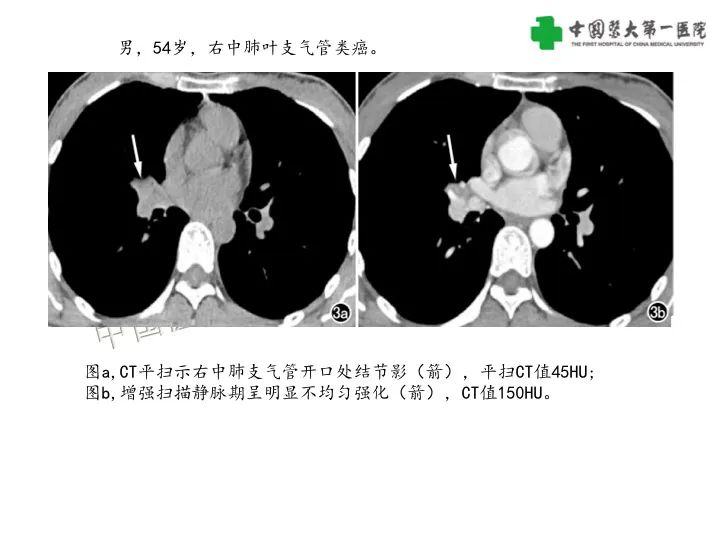

【病例】气管腺样囊性癌1例CT影像-4

【病例】气管腺样囊性癌1例CT影像-5